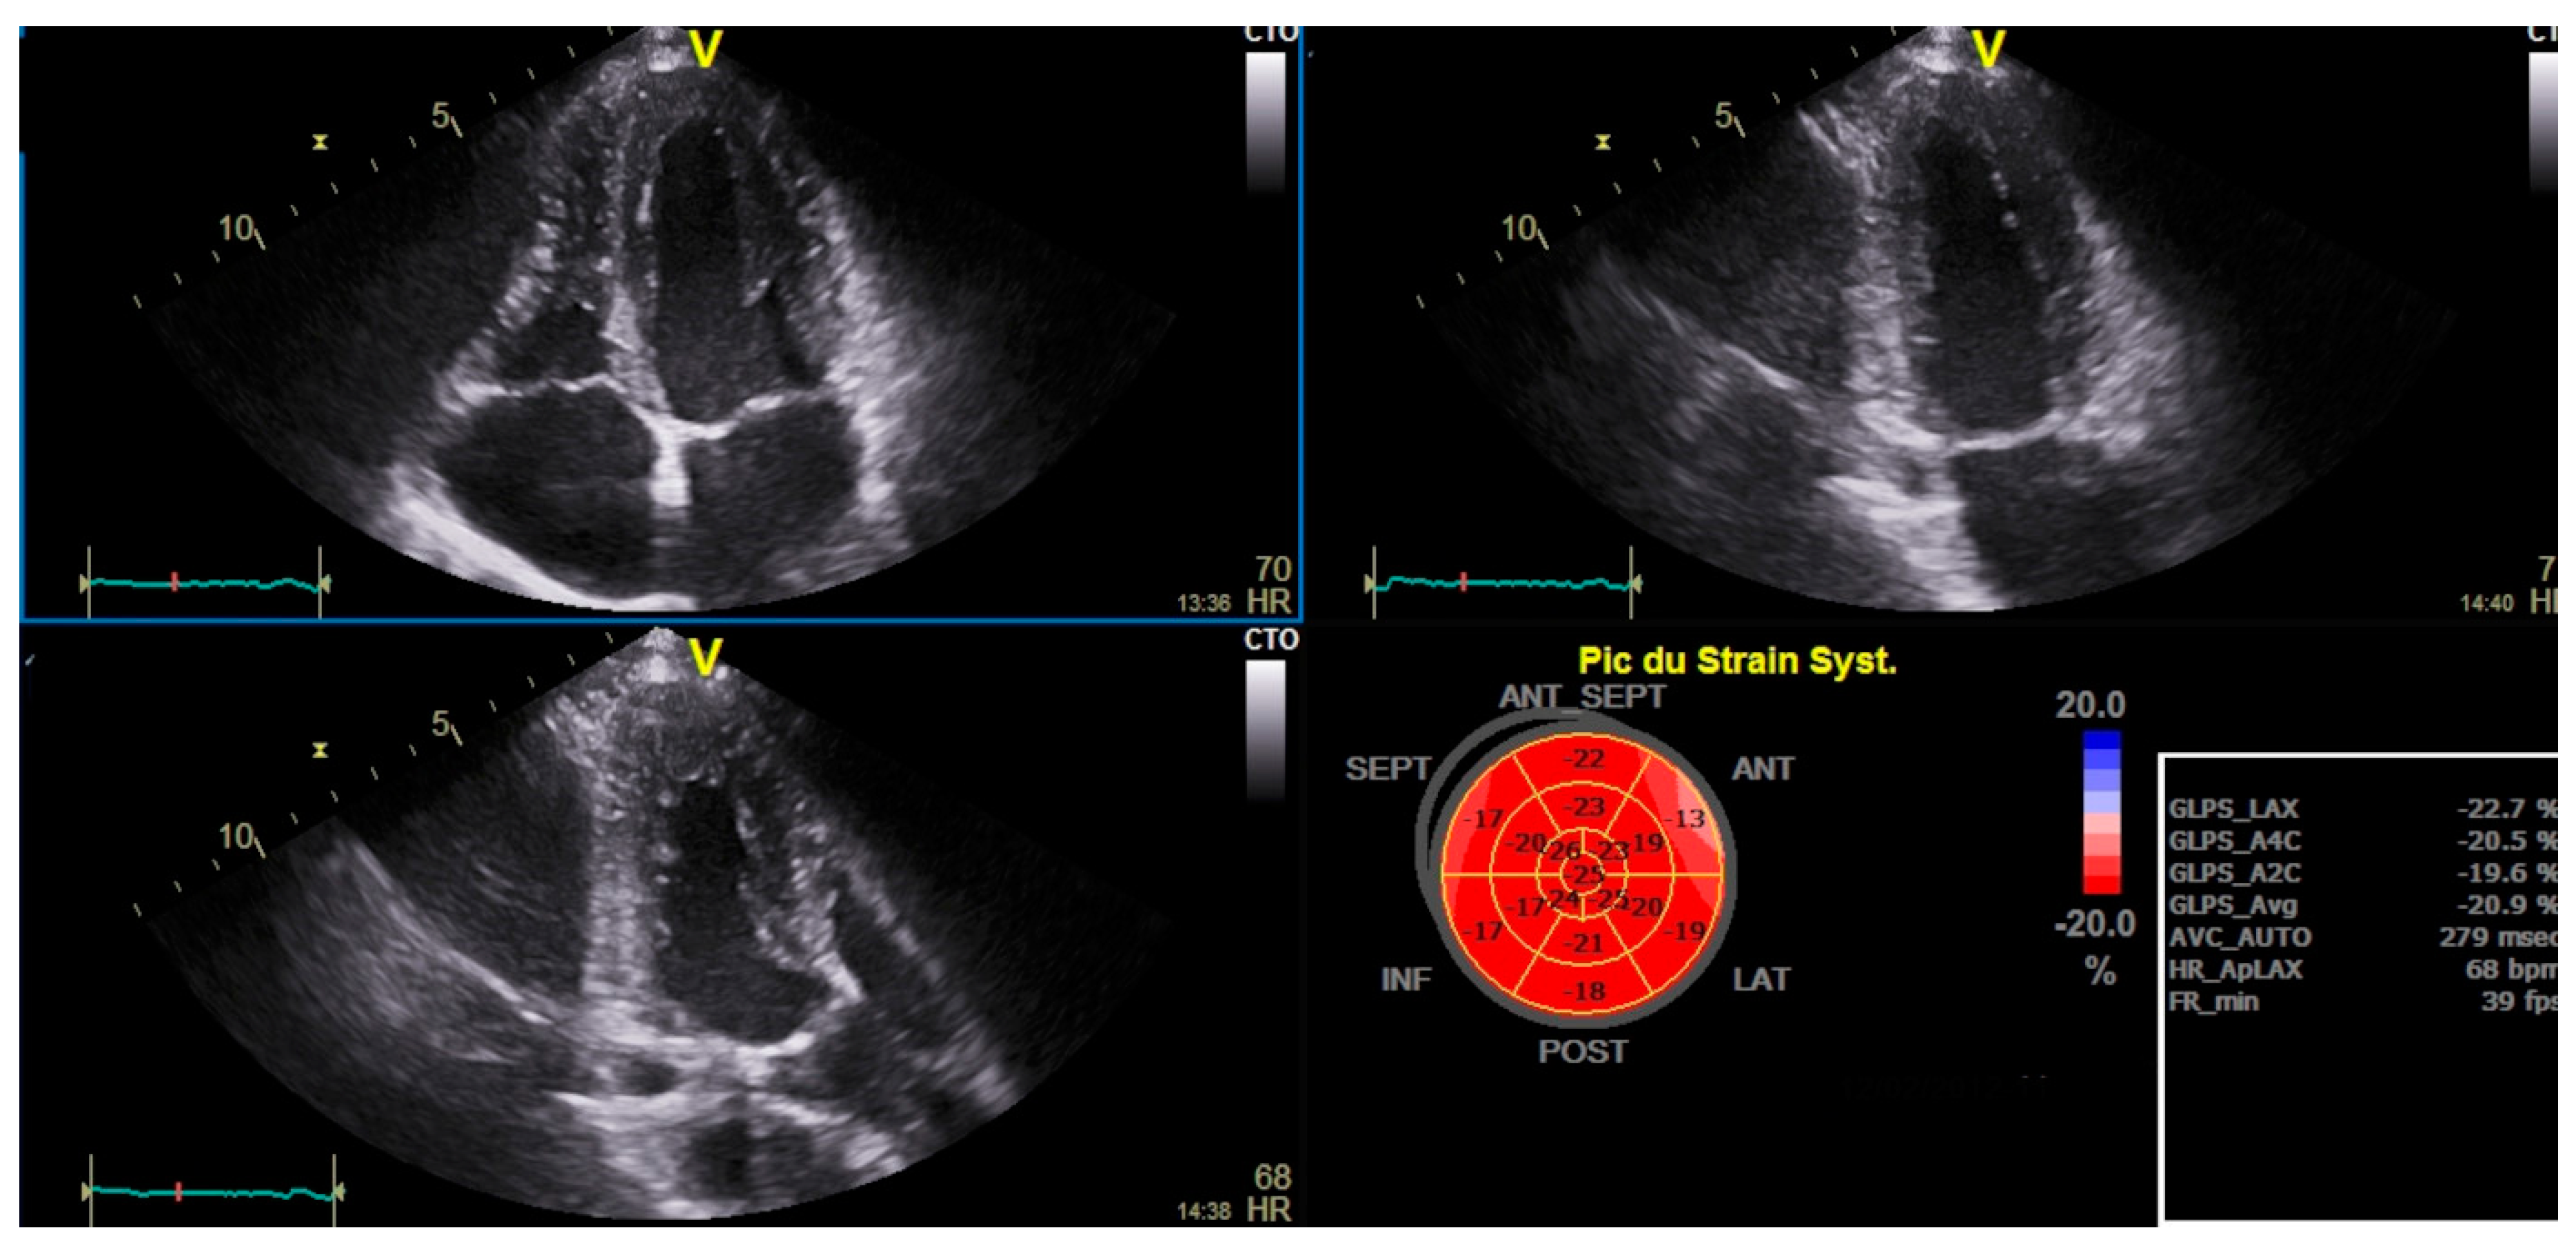

| RV Strain (%) | -19.9±3.7 |

| LV GLS (%) | -21.1±2.4 |

| Characteristics | Normal RV Strain (N=32) N (%) Or Mean±SD | Impaired RV Strain (N=48) N (%) Or Mean±SD |

P |

|---|---|---|---|

| Characteristics | Normal RV strain (N=32) Mean±SD | Reduced RV Strain (N=48) Mean±SD | p |